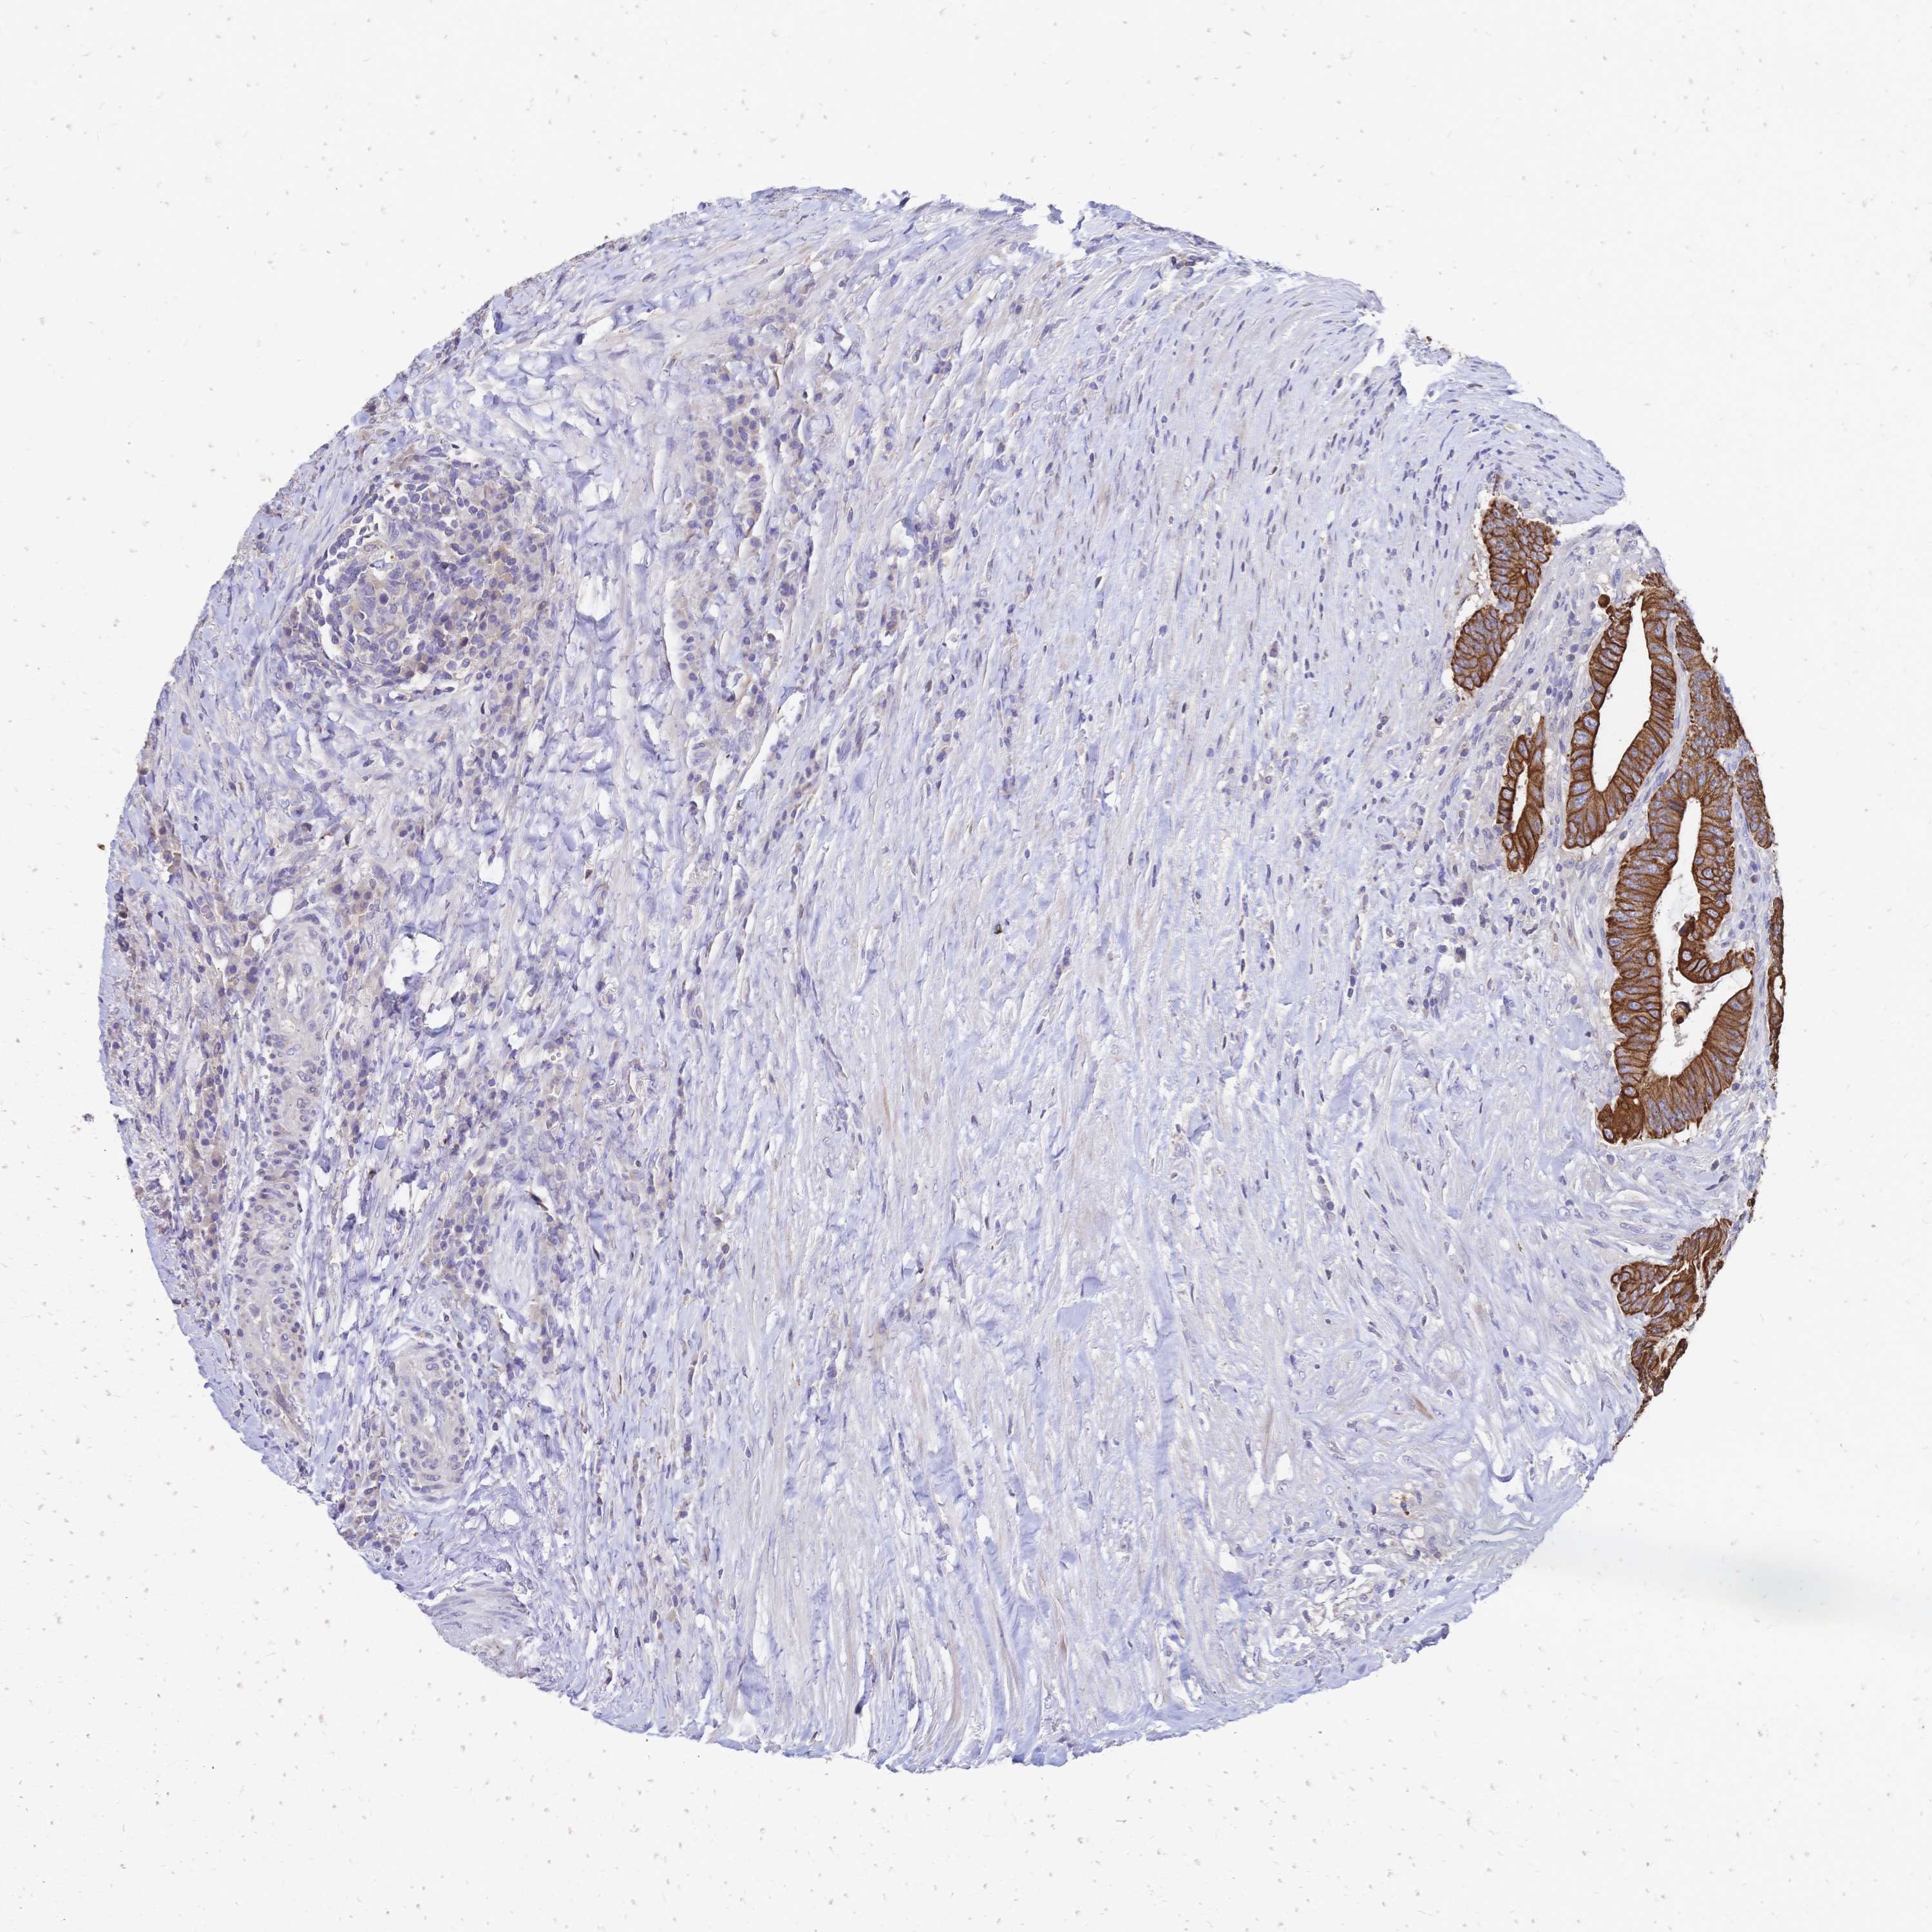

CANCER COLORECTAL CANCER Show tissue menu

COAD TCGA COAD VALIDATION READ TCGA READ VALIDATION PROTEIN COAD CPTAC PROTEIN EXPRESSION

ANTIBODIES

AND

VALIDATION